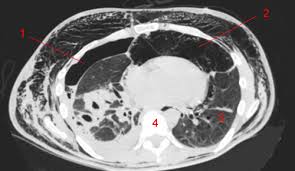

Une irm thoracique sans injection (figure 4) effectuée à titre complémentaire a mis en évidence cette même masse paravertébrale bilatérale hétérogène la myélofibrose pouvait aussi être discutée du fait de la haute densité osseuse au scanner, mais il n'y avait aucun argument biologique en ce sens. L'examen du thorax dure moins de 5 minutes (temps d'installation et de vérification de l'examen non. Le scanner est l'examen de base. Survient dans 18% des traumatismes de la rate. Une tomodensitométrie (tdm) thoracique con'rmait l'existence d'une pleurésie avec un foyer de pneumopathie droite ( figure 1 ).

Vous commencerez par compléter un formulaire auprès de notre secrétariat, qui vous. Hospitalisation pour un asthme négligé. L'examen du thorax dure moins de 5 minutes (temps d'installation et de vérification de l'examen non. Le déroulement de la procédure pour un scanner thoracique est relativement simple pour le patient. Le scanner thoracique permet d'examiner sur des coupes transversales fines les poumons, leur enveloppe appelée plèvre, et les vaisseaux qui irriguent les bronches et les poumons. The sql injection scanner (light scan) performs a quick and fast scan of a target url that allows it to identify vulnerabilities in web applications. Dans de nombreux cas, le scanner thoracique requiert l'injection préalable d'un produit de contraste afin d'améliorer la lisibilité des images et de détecter plus aisément une anomalie. Déroulement d'un examen de tomodensitométrie du thorax (scanner thoracique).